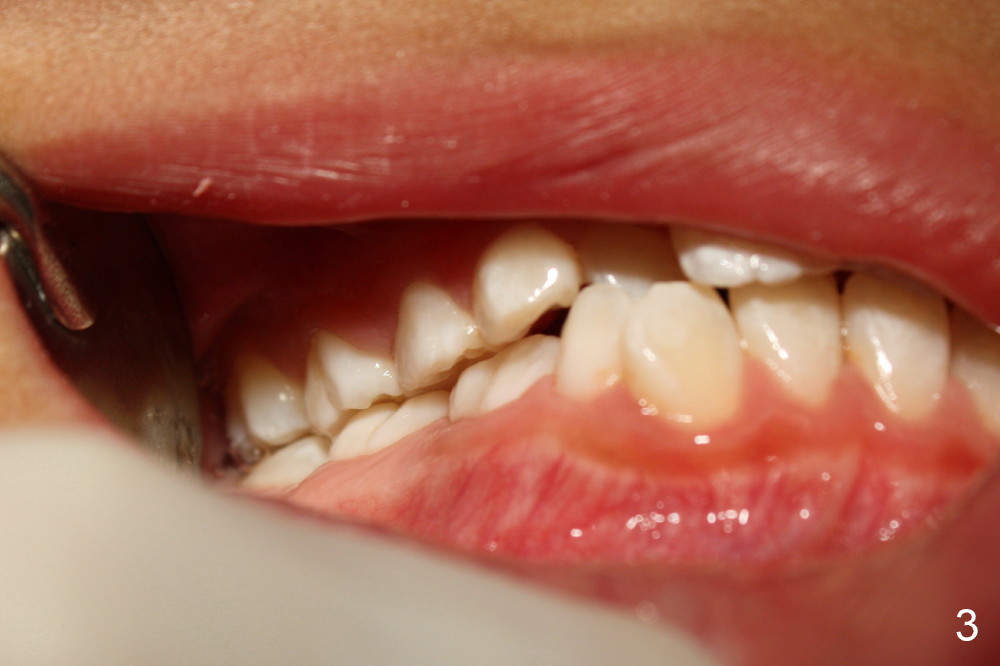

Six months earlier, the tooth #7 is erupting lingually. Now at the age of 8, both of the upper lateral incisors are in cross bite (Fig.1*). It appears that the cross bite is due to jaw deficiency in anteroposterior direction. In fact, these two laterals are blocked because there is not enough space transversely (Fig.2). Posterior occlusion is Class I bilaterally (Fig.3,4). The lower incisors are also crowded. Therefore early comprehensive orthodontic treatment has the most important component: palatal expander. In our previous case, unilateral cross bite resolves rapidly after the palate is expanded.